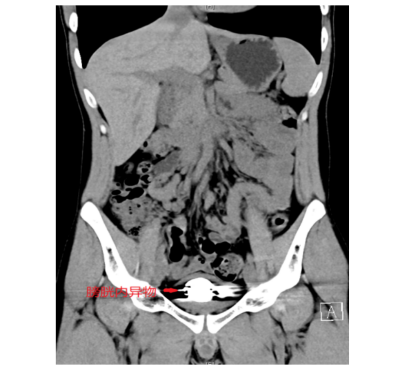

据了解,22岁的简轩(化名)因尿频、尿急、尿痛持续一年,近期症状加重才前往香港马会app

(南华大学附属香港马会app

)泌尿外科就医,经影像学检查发现,其膀胱内竟积聚大量直径约5毫米的金属圆珠,排列紧密且表面已形成钙化外壳。该院泌尿外科一区主任傅发军及其团队结合病史及临床经验判断异物为数十颗磁性钢珠,如不及时取出,长期滞留可能导致尿路梗阻、感染甚至组织损伤。